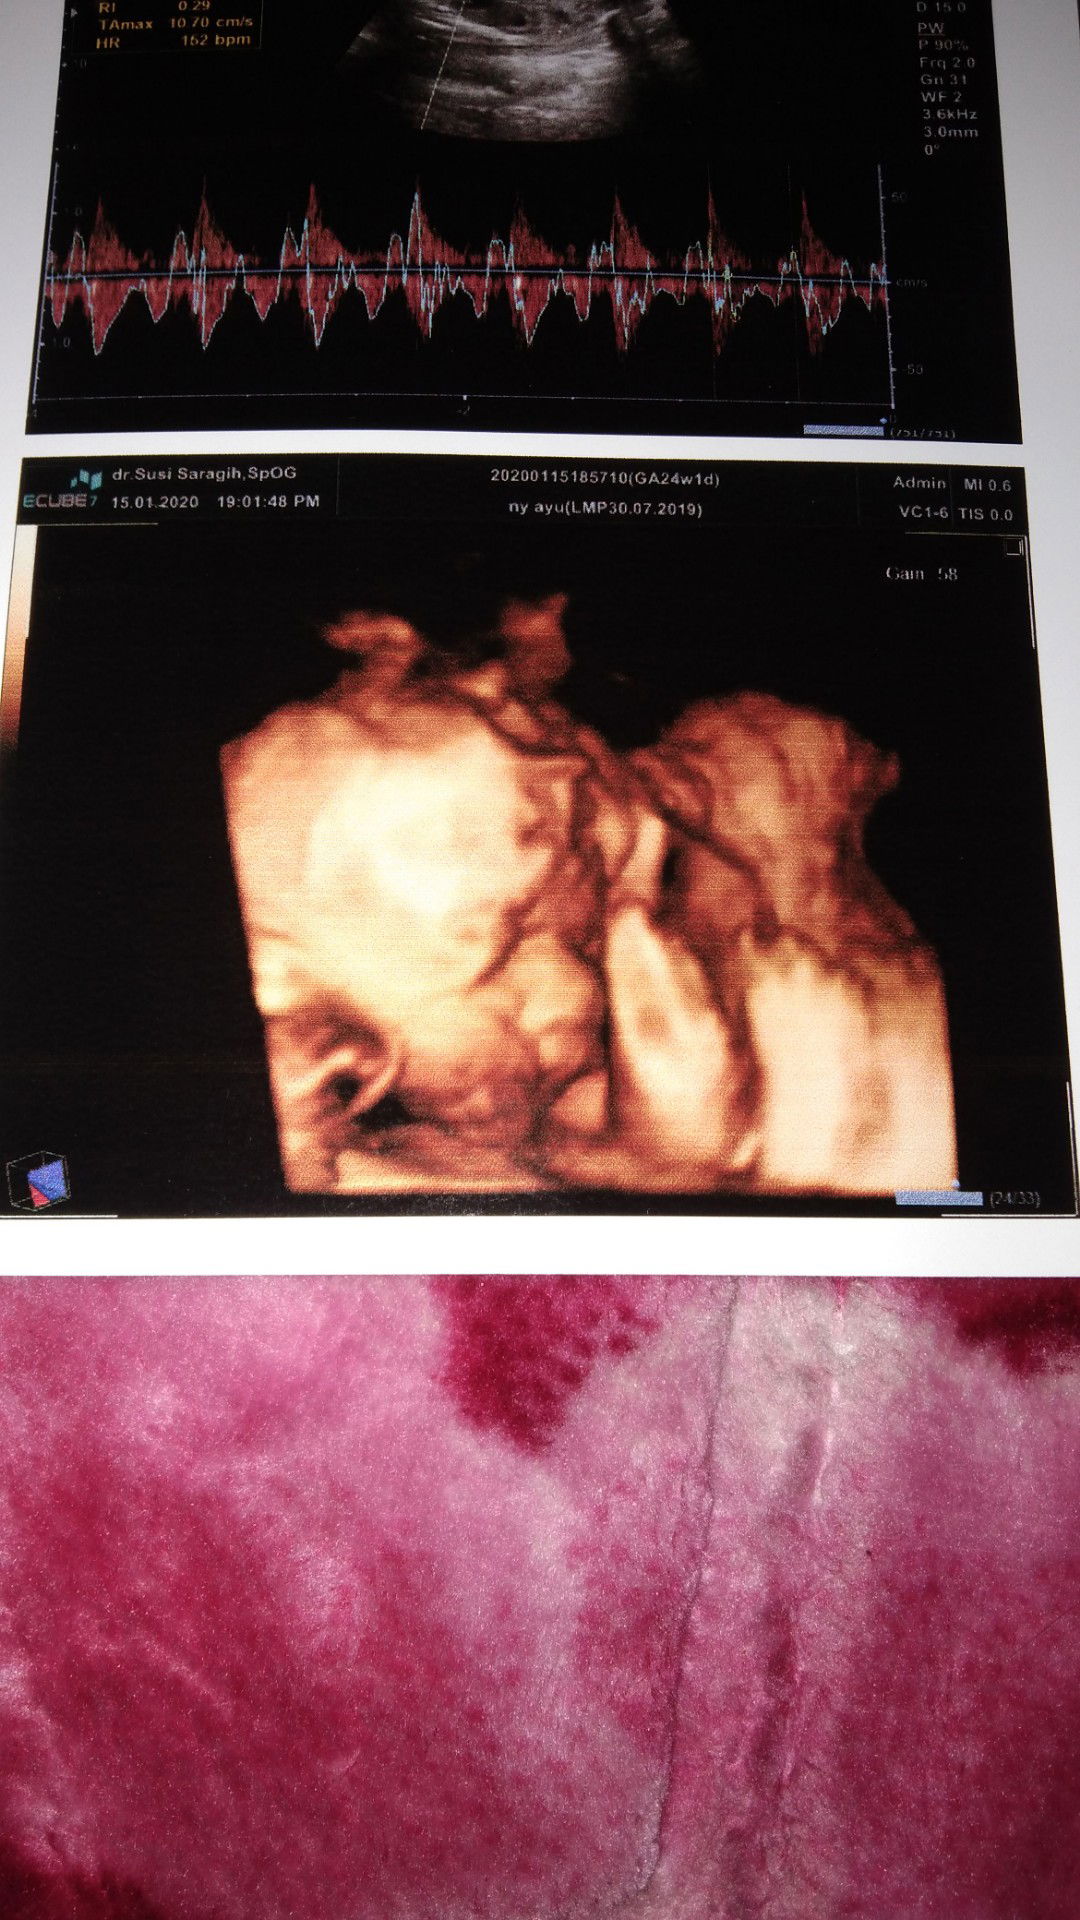

24week

udah kliatan jls mukanya.. :') bbj 710gr